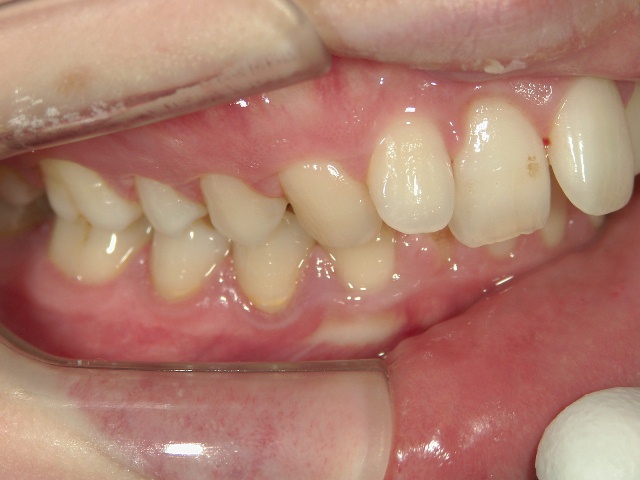

矯正歯科 治療前 右

矯正歯科 治療前 左